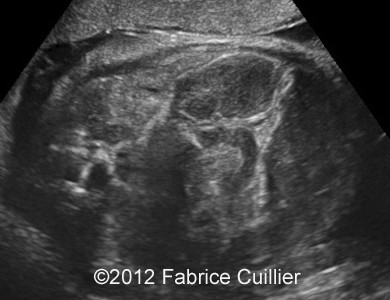

At 32 weeks, the aspect of the intestinal dilatation changed. Low digestive obstruction was suspected (Image 2, 3), with important aggravation at 35 weeks (Image 4). Mesenteric artery and vein had a physiological position (Image 5). Fetal ears and face were normal. Corpus callosus was present (Image 6). The extremities were also normal. Sex was male with bilateral hydrocele (Image 7). Abdominal fetal MRI was performed (Image 8, 9).

At 38 weeks, the dilatation has increased with significant meconium retention.

Image 10, 11: At 38 weeks, dilatation has increased with significant meconium retention.

8B

8D